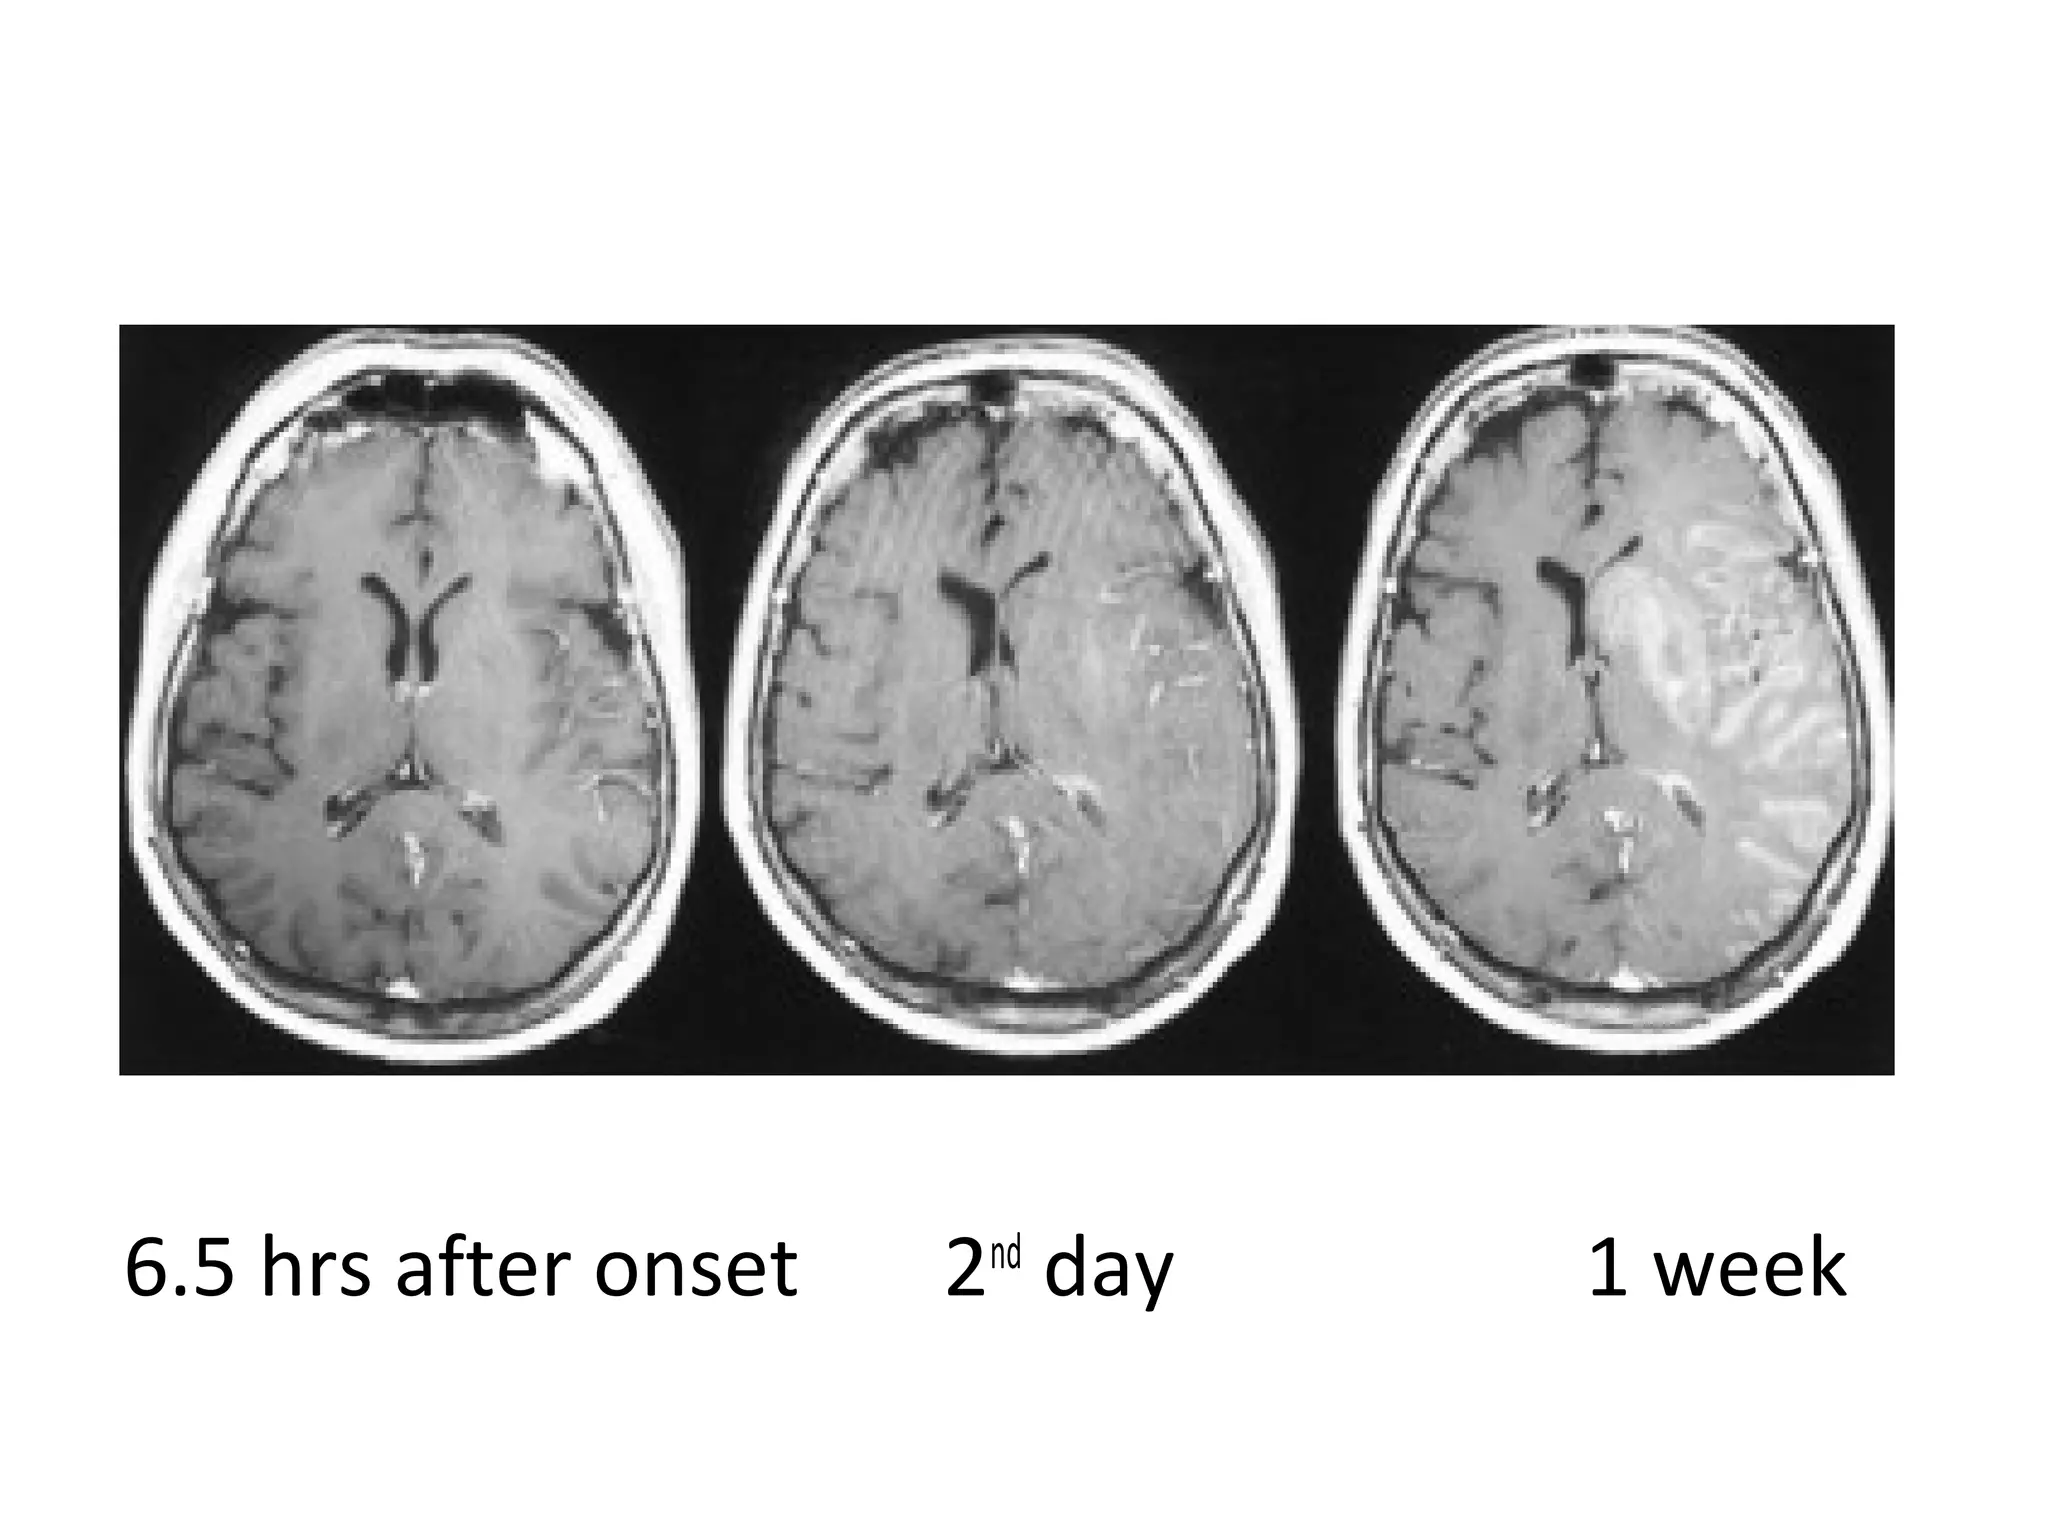

8 hrs after onset 2nd

day 1 week

6.5 hrs after onset 2nd

15 hrs after onset 2nd

23 hrs after onset 2nd